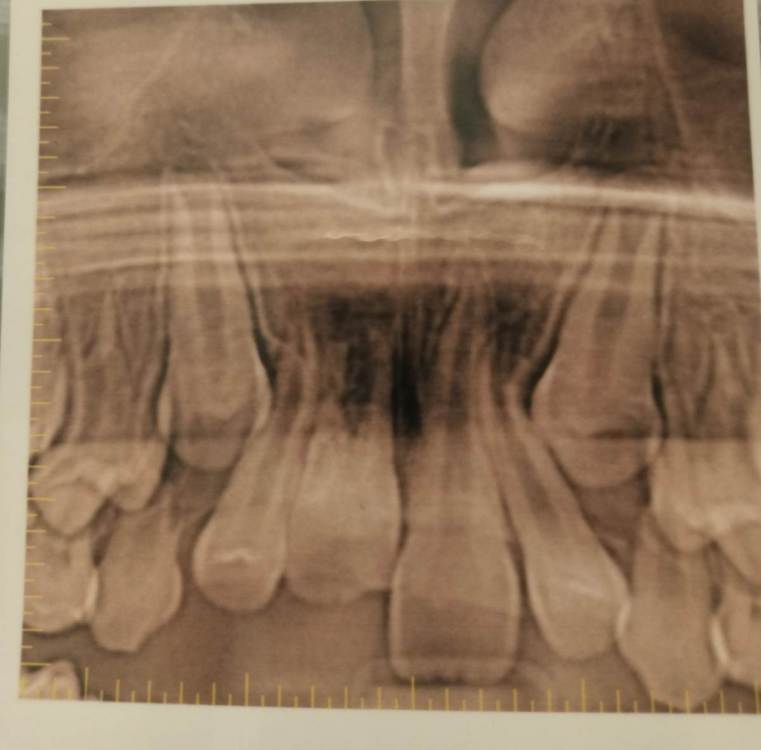

Pole4ka Опубликовано 4 июля, 2021 Поделиться Опубликовано 4 июля, 2021 Добрый день уважаемые специалисты. Три года назад у сына произошла травма, в возрасте 8 лет. Был выбит передний зуб, сломан альвеолярный участок кости. В нашем населённом пункте не было ни одного специалиста, который мог бы помочь в этой ситуации. Через три часа после травмы, были направлены в челюстно-лицевую хирургии в другом городе. Выбитый зуб находился в физрастворе. В итоге, была сделана операция, реплантирован зуб (верхушка зуба на тот момент была не сформирована), добавили костную ткань в месте перелома альвеолярной кости,наложили швы, поставили шины и вывели зуб из прикуса. В течение месяца наблюдались каждый день. Соблюдали все рекомендации по питанию и санации полости. В итоге, зуб прижился. Зуб не депульпировали! На сейчас он ничем не отличается от соседних, единственное, ушел вверх. Через год после травмы поставили расширительные пластины. Т. к. плюс ко всему у нас открытый прикус. Два года пластин. На сейчас ждем полной смены зубов и установки брекетов. Вопрос следующего характера, что можно сказать о текущем состоянии реплантированного зуба и какие шансы его дальнейшего пребывания в полости рта? Есть ли резорбция и другие какие-то минусы? Повторюсь - зуб был не сформирован (верхушка открыта и доктор дал шанс на ревитализацию пульпы). Всем спасибо! Так было ровно год назад Ссылка на комментарий

wladdX Опубликовано 4 июля, 2021 Поделиться Опубликовано 4 июля, 2021 Насколько могу судить по приложенным скринам, резорбция корня всё же есть. Судя по Вашему рассказу, проведённая коллегами работа была верной, результат весьма неплохой. Рассчитывать на длительное пребывание зуба 11 в челюсти не приходится. Когда-то его придётся удалить. 1 1 Ссылка на комментарий

Pole4ka Опубликовано 4 июля, 2021 Автор Поделиться Опубликовано 4 июля, 2021 38 минут назад, wladdX сказал: Насколько могу судить по приложенным скринам, резорбция корня всё же есть. Судя по Вашему рассказу, проведённая коллегами работа была верной, результат весьма неплохой. Рассчитывать на длительное пребывание зуба 11 в челюсти не приходится. Когда-то его придётся удалить. Спасибо большое за Ваше мнение и отклик! Нам бы дотянуть до момента, когда можно будет ставить имплант. Честно говоря, особой разницы между прошлогодним снимком (нижним среди снимков) и панорамным не вижу, поэтому возникла надежда, что резорбция приостановлена. А анкелоза нет? Спасибо! @wladdX Спасибо!!! Ссылка на комментарий

Pole4ka Опубликовано 4 июля, 2021 Автор Поделиться Опубликовано 4 июля, 2021 И ещё один момент, нельзя ли списать такой вид корня на снимке (с учётом того, что за два года особых явных изменений нет, во всяком случае визуальных), на то, что зуб был все таки не сформированный? Ссылка на комментарий

wladdX Опубликовано 5 июля, 2021 Поделиться Опубликовано 5 июля, 2021 Резорбция корня + вертикальное расположение = анкилоз. То что зуб был с несформированной верхушкой корня помогло ему простоять так долго после реплантации в растущей челюстной кости. Конечно, хорошо бы, чтоб зуб смог простоять до имплантации, но на мой взгляд это маловероятно. 1 1 Ссылка на комментарий

Bier Опубликовано 6 июля, 2021 Поделиться Опубликовано 6 июля, 2021 Я вас не порадую: 1. Зуб анкилозирован. 3 часа в физрастворе = нет шансов на реваскуляризацию пульпы и связки. Судя по вашим снимкам однозначно анкилозирование. 2. Что делать теперь и почему: Зуб начал отставать в росте, еще через несколько лет это превратится в нерешаемую эстетическую проблему (вся челюсть будет расти, а зуб и участок челюсти с зубом - нет). Необходимо провести операцию декоронации (спилить коронковую часть зуба глубже уровня костной ткани, удалить то, что осталось от пульпы и дать так зажить. Остатки корня резорбируются сами с замещением на кость. Зато челюсть будет расти вместе с отстальными зубами. восстановить зуб временно на пластике (съемной) потом на брекетах. Имплантация желательно не раньше 21 года. Оставлять так нельзя! Ссылка на комментарий